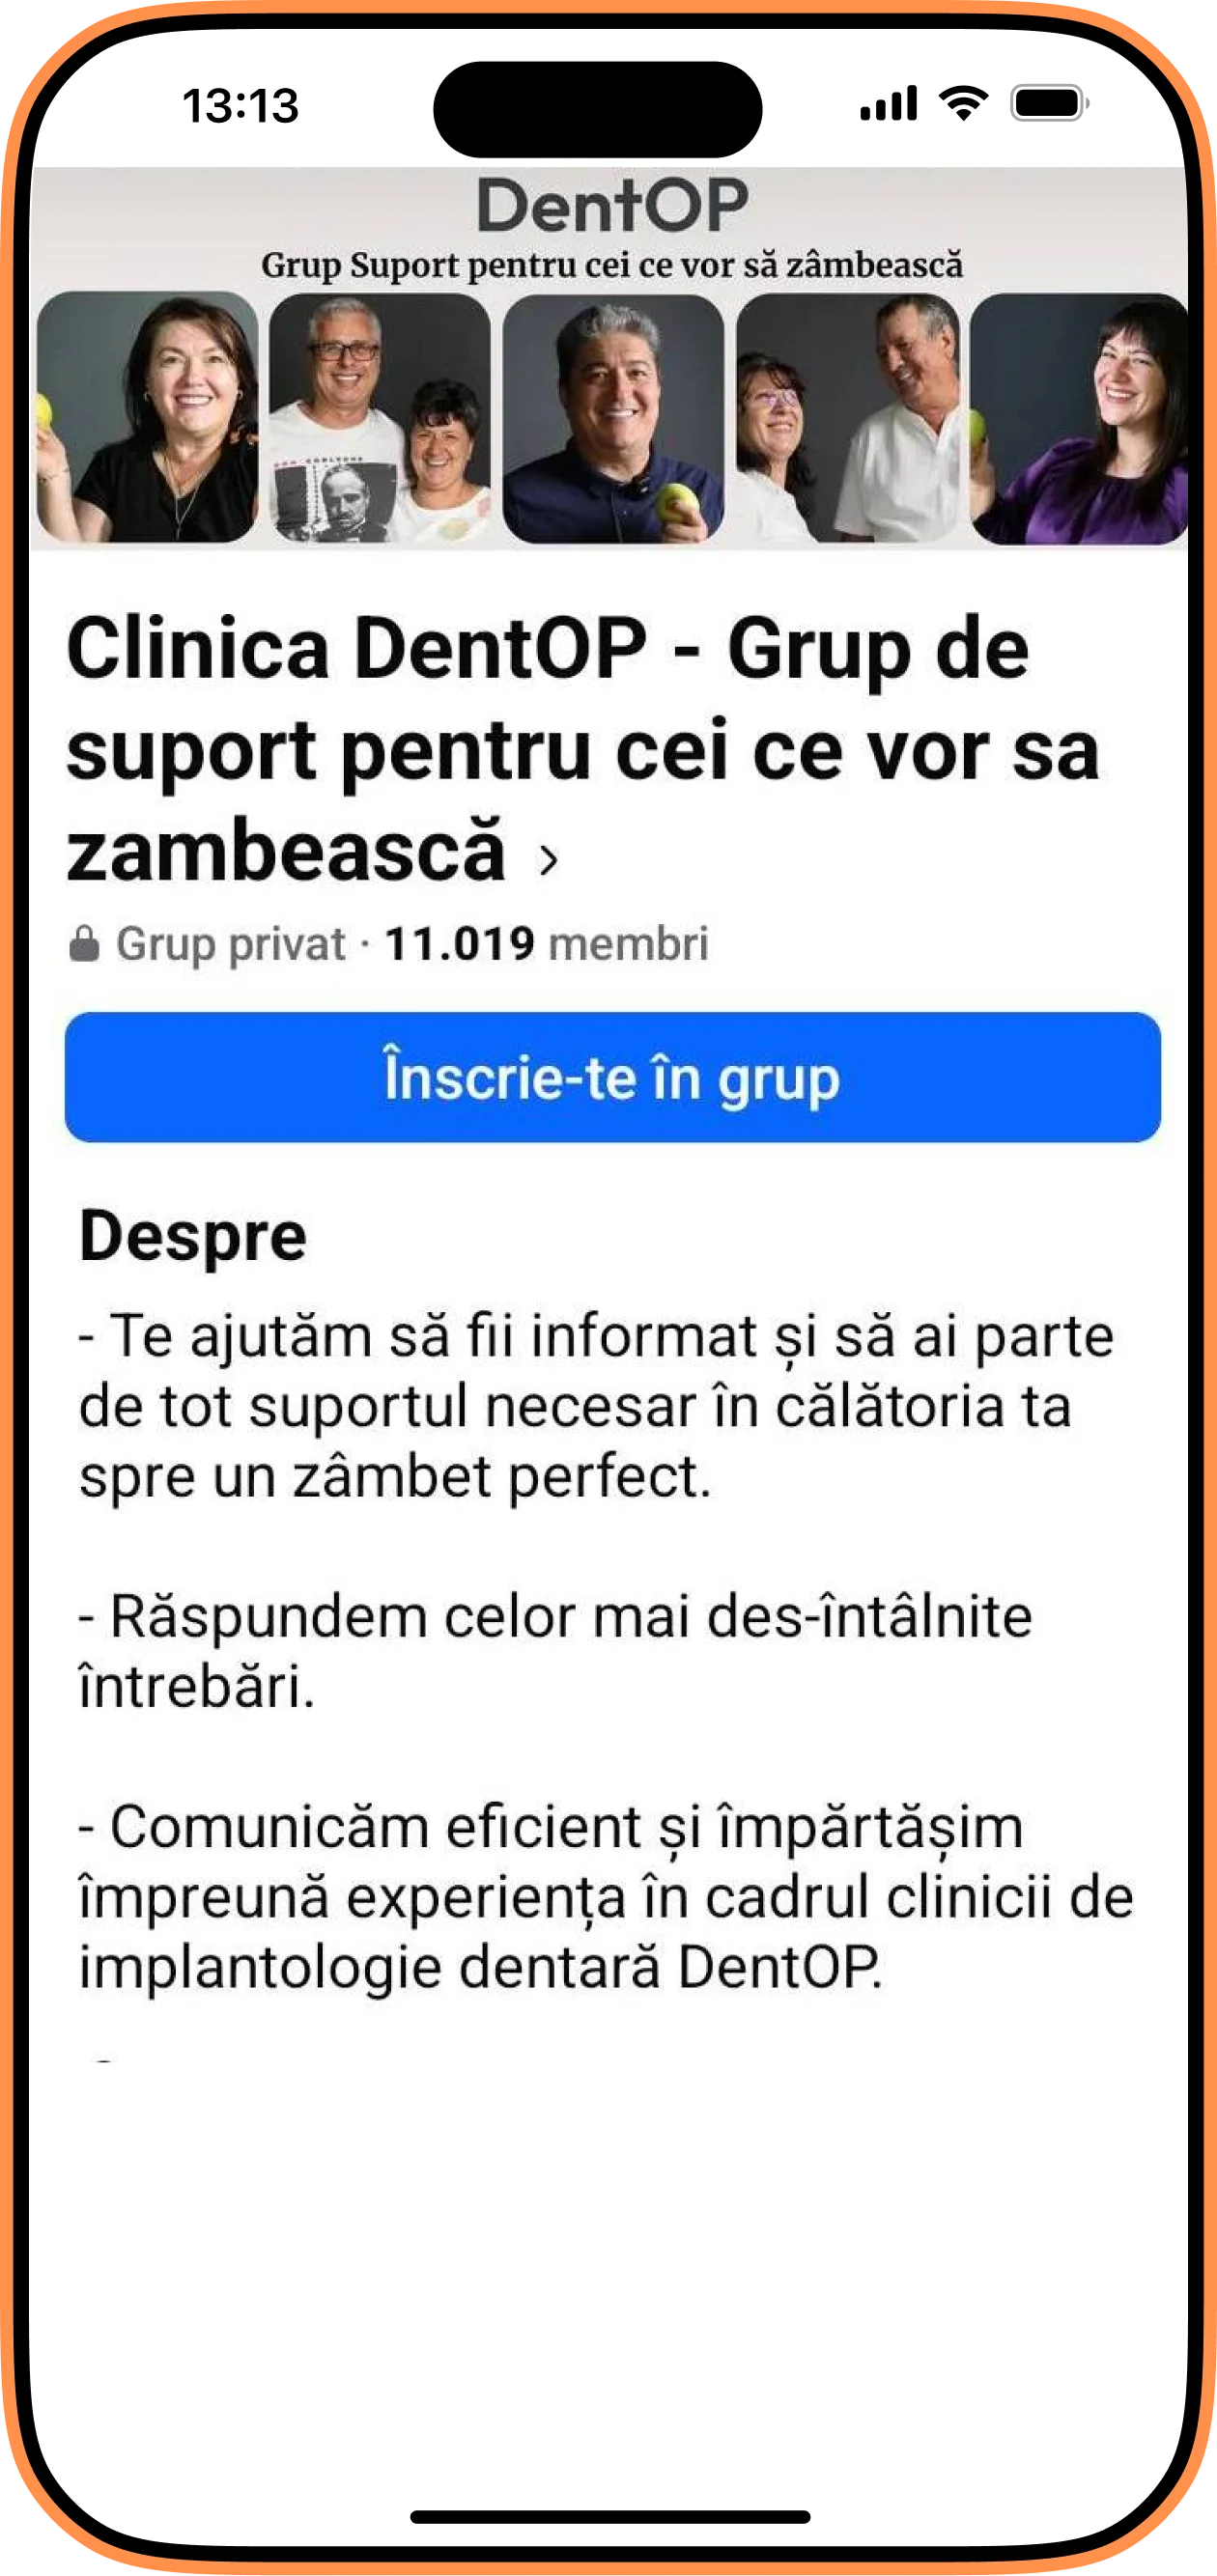

Cu ajutorul Computerului Tomograf, Dr. Cazacu Corrado a observat că oferta osoasă limitată nu îl va ajuta destul în reabilitarea danturii. În astfel de situații apelăm la procedura de adiție de os pentru a putrea fi inserate un număr optim necesar de implanturi dentare.

În radiografia de mai jos putem observa cele 6 implanturi la maxilar. La mandibulă au fost inserate un număr de 5 implanturi dentare pentrui a crea sprijin pentru dantura fixă.

În doar 24h i-au fost inserate și lucrările provizorii pe implanturi. Pacienta le-a purtat aproximativ 6 luni, iar acum a beneficiat și de lucrările finale menite să o însoțească pentru cât mai mult timp.